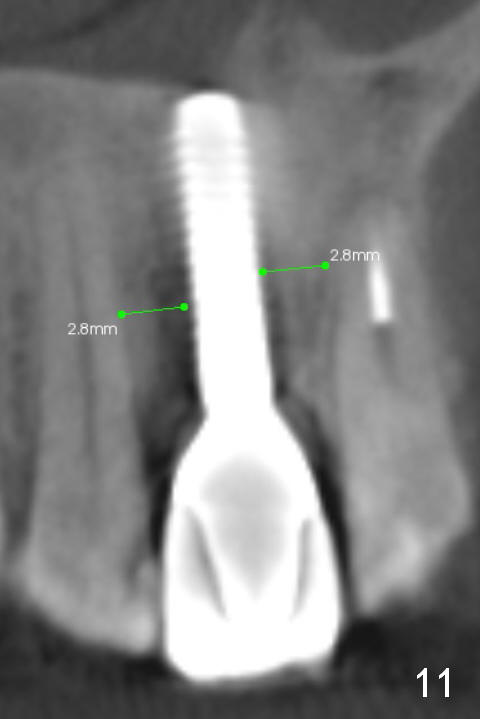

Fig.10 is a sagittal section of the implant (arrowheads: nasal floor). It is apparent that there is enough space (Fig.11,12 (PA)) for osteotomy (Fig.13 red lines: A: angled Titanium abutment). With the palatal mucoperiosteal flap attached the implant/bone segment, it is moved apically (Fig.14). Coronally the coronal portion is repositioned palatally while the apical portion buccally (Fig.15 arrows). Is the segment stable?